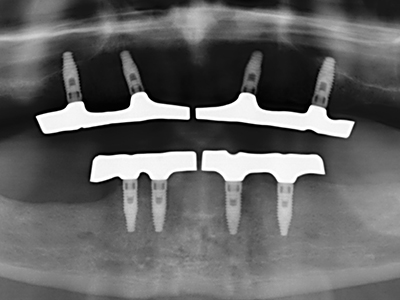

Както е показано в миналото, всяка костна хирургия представлява възможна индикация за пиезохирургия. По този начин, за препарацията на подвижни сегменти в остеогенеза (Фиг. 23-25) и остеотомия се използват специални накрайници, без да се застрашава снабдяването с кръв в кресталната зона, което е от съществено значение за успеха и на двете техники (Gonzalez-Garcia, Diniz-Freitas et al. 2008).